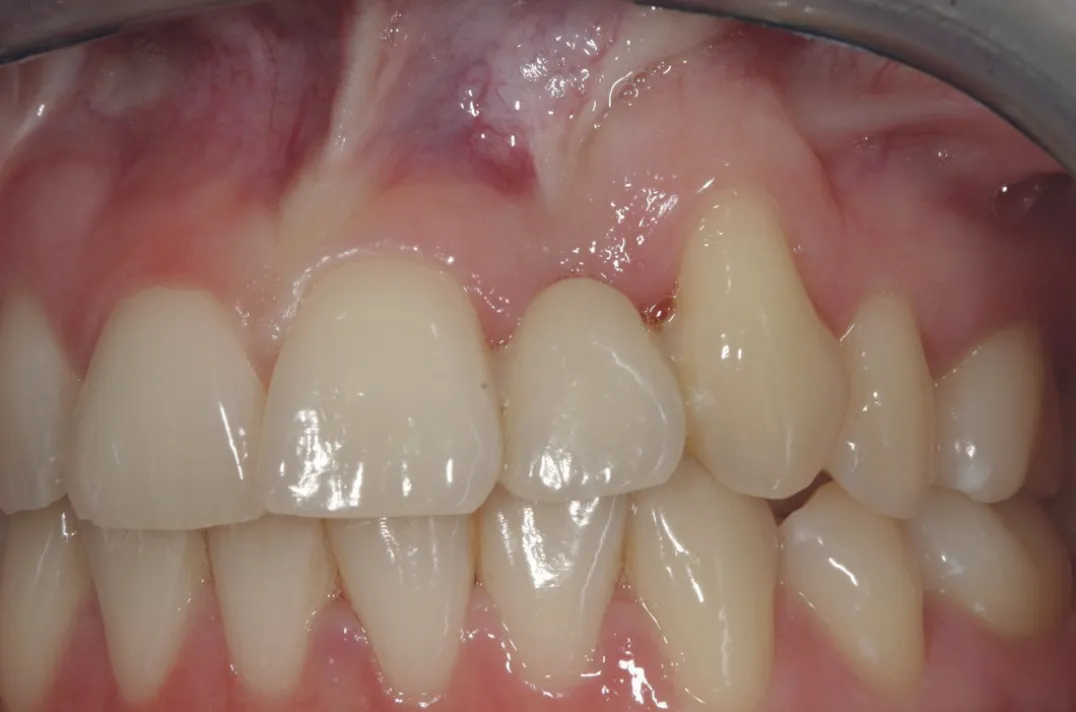

图 21 :术前临床检查。

图 48 :术后 1 年口内情况。